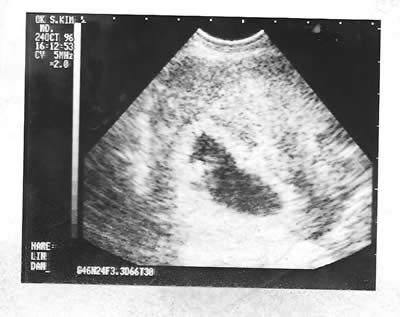

B超照片(1996年10月24日和1997年4月1日)。拜现代技术之赐,人在母腹中就可以留影。虽然影像看起来不甚清楚,医生却能告诉你这是一个健康的男孩。想当初那种喜悦之情,真是难以言表。